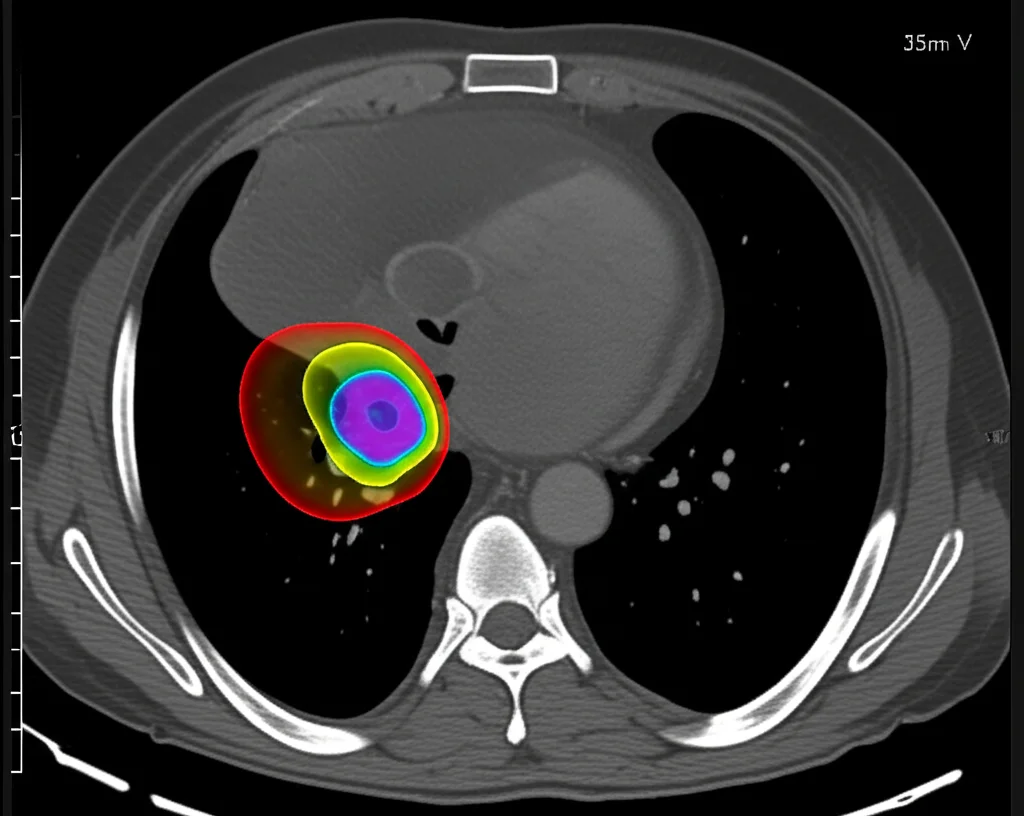

Ciao a tutti! Oggi voglio parlarvi di una cosa che mi sta molto a cuore e che, credetemi, potrebbe fare una bella differenza per chi si trova ad affrontare il cancro al polmone non a piccole cellule in stadio iniziale: la radioterapia corporea stereotassica (SBRT). È una tecnica pazzesca, super efficace e minimamente invasiva. E quando la combiniamo con la terapia ad arco volumetrico modulato (VMAT), soprattutto usando fasci senza filtro di appiattimento (FFF), otteniamo una precisione nel colpire il tumore e una rapidità di trattamento davvero notevoli.

Ecco, la domanda che ci siamo posti è: possiamo semplificare la VMAT mantenendo una qualità dosimetrica eccellente? È qui che entra in scena la d-VMAT, una versione semplificata della VMAT convenzionale (c-VMAT), che si basa su una distribuzione di dose simile a quella della terapia ad arco conformazionale dinamica (DCA) e un controllo più stringente sulla forma delle aperture. L’idea è di ridurre la complessità, il che potrebbe tradursi in meno “Unità Monitor” (MU) – in pratica, meno “benzina” per l’acceleratore – e tempi di trattamento più brevi.

Abbiamo preso in esame, retrospettivamente, i dati di 20 pazienti con tumore al polmone non a piccole cellule, non operabili. I loro PTV variavano parecchio, da circa 7 a quasi 70 cm³. La dose prescritta era di 48 Gy in quattro frazioni, con l’obiettivo di coprire il 95% del PTV. Per ogni paziente, abbiamo creato piani di trattamento sia con d-VMAT che con c-VMAT, testando diverse PIL: 60%, 70%, 80% e 90%.